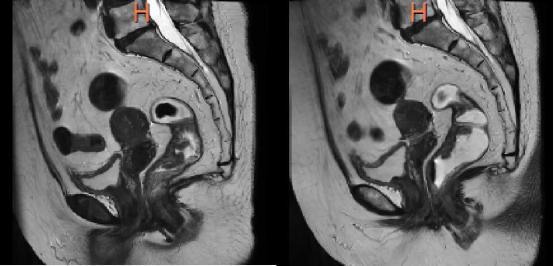

那大家肯定想说现代医学这么发达,超声、CT、肠镜各种检查方式都能应用于直肠,为什么医生会建议让我做直肠磁共振。那CT的优势是检查速度比较快,更适合于急诊的时候,并且它有辐射,展现出来的清晰度也比较低。肠镜通过内镜进入身体里,确实可以将内部的肿块等看得很清楚,零距离观察黏膜,对于疑似病变区域还可以直接取组织进行活检,但是它是有创检查且主要观察肠腔内侧,无法评估肠壁外的侵犯程度。直肠磁共振是目前唯一可以一次性评估所有关键因素的检查。首先直肠磁共振是无创的,这让受检者不承受太多痛苦;再来它可以清晰区分直肠壁各层结构(黏膜、肌层等),很好的显示肿瘤的深度和淋巴结的转移情况,它对于直肠癌的患者来说具有重要意义,同一个患者可以根据需要反复检查因为没有辐射,对身体不造成损伤;其次是因为它能对直肠癌进行术前精准分期,帮助临床在制定手术方案的时候提供有力依据,判断是否保住肛门,这对直肠癌患者之后的生活质量有着很大意义。除此之外,它还具有三维立体成像功能,可以多角度观察直肠壁,发现微小病灶,对于克罗恩病能够准确找到肠壁增厚部位,瘘管等。当然它也有自己的缺点,在于费用比较高昂,检查时间比较久,整个检查可能需要30分钟~45分钟不等。我们可以通过图片清晰感受下对于肿块显示的清晰度。

打开网易新闻 查看精彩图片